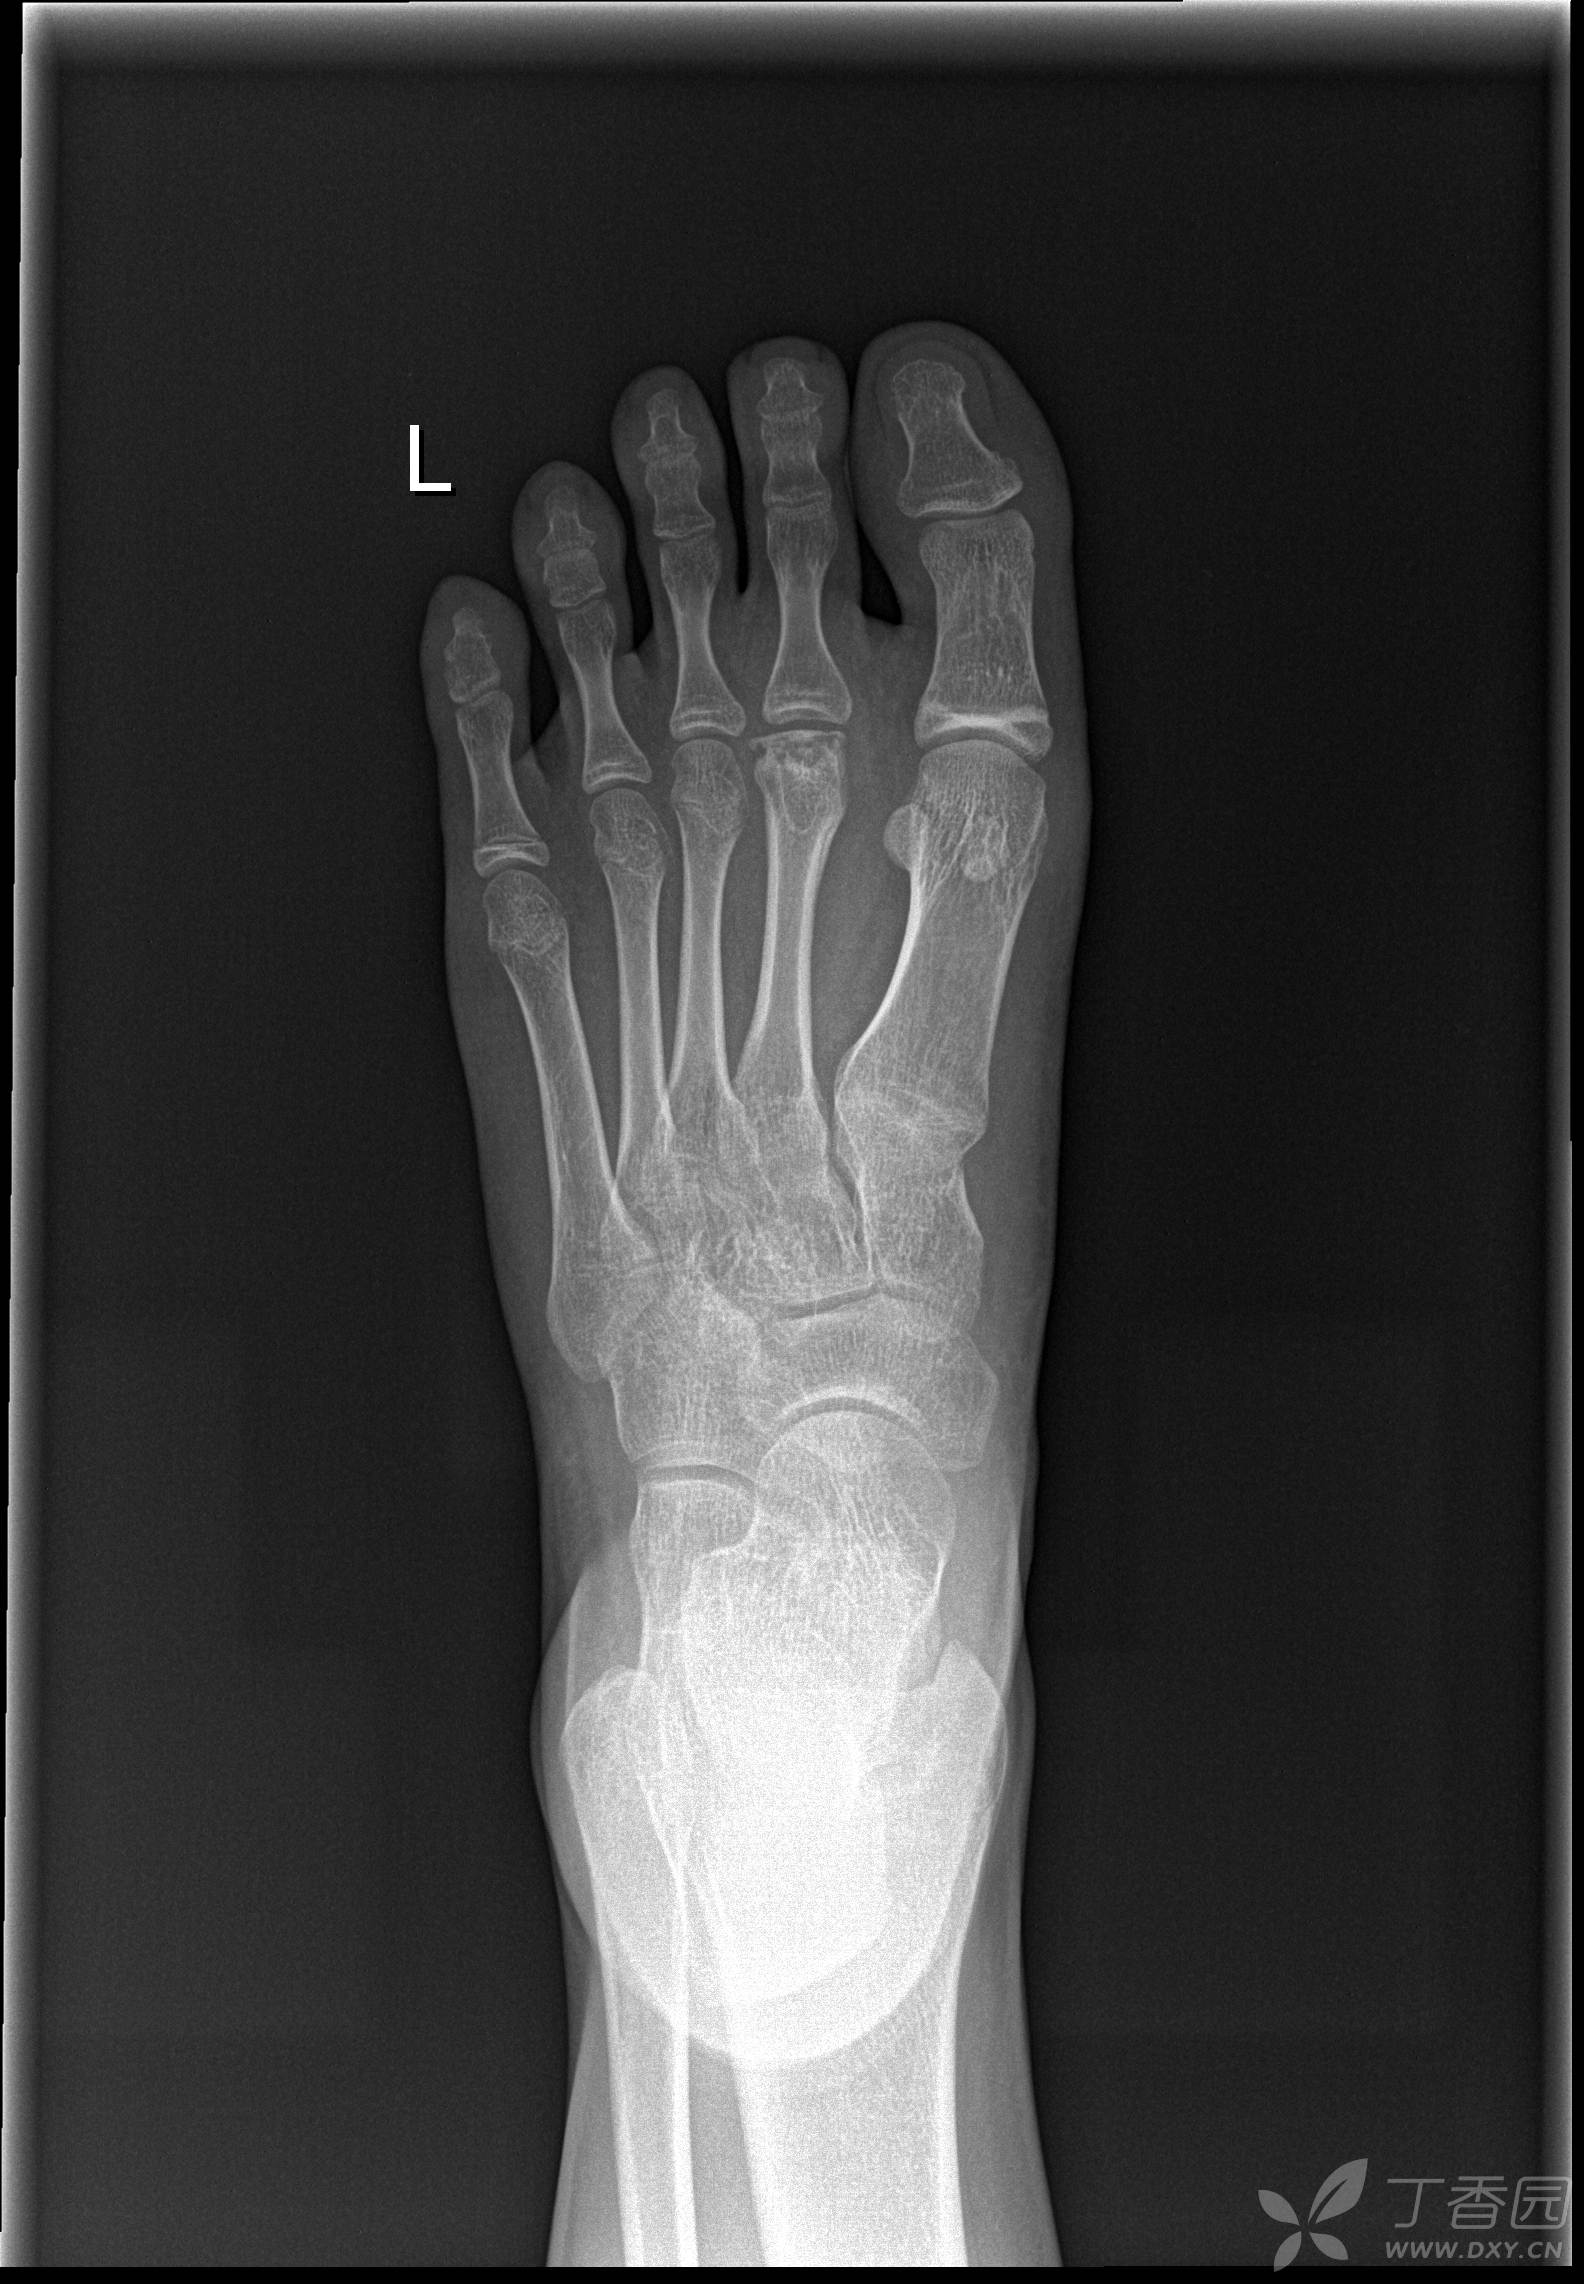

跖骨骨折

跖跗关节完全脱位伴第2,4跖骨头骨折

跖骨头骨折.闭合内固定

跖骨头缺血坏死补充一例.